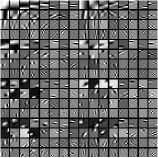

Recall that in Section IV.F, we used the transforms learned from the patches of the XCAT phantom volume to perform reconstruction of the chest volume from helical CT data. Alternatively, one could learn the transforms from the patches of the PWLS-EP reconstruction of the helical CT data. Fig.Β 14 shows the union of transforms () learned from patches of the XCAT phantom and the PWLS-EP chest reconstruction, with . These two union of transforms display some similar types of features, and provide similar visual reconstructions in PWLS-ULTRA (with patch-based weights ) in Fig.Β 14. Thus, the transform learning algorithm extracts quite general and effective sparsifying features for images, without requiring a very closely matched training dataset.